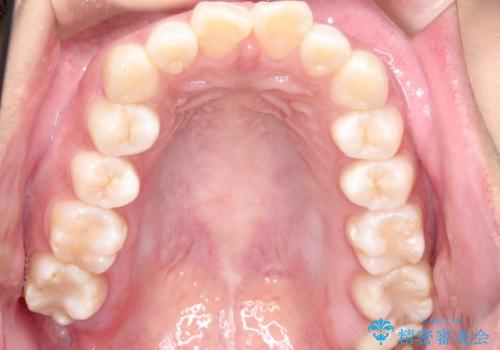

上の歯の前から4番目の歯を2本抜歯して、そのスペースに前歯を移動させて、前歯を引っ込める計画としました。

抜歯をすることでしっかり前歯を後方に移動させて、引っ込めることができました。